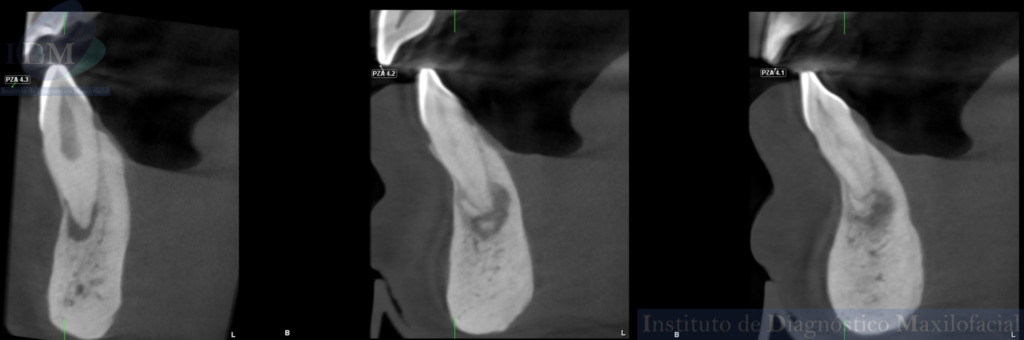

Así mismo en la tomografía volumétrica de haz cónico de campo reducido evidenciamos que dichas imágenes mixtas se encuentran comprometiendo zona a pical de la pieza 41 y 42 con un aumento de la densidad ósea adyacente. Siendo la imagen hipodensa a nivel a pical de la pieza 43 una probable lesión apical.

CORTES TRANSAXIALES